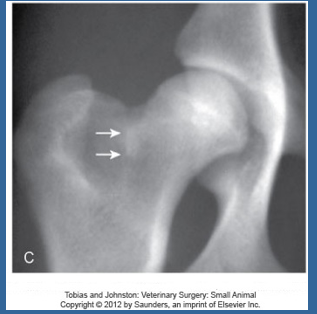

What are the typical radiographic findings of hip dysplasia?